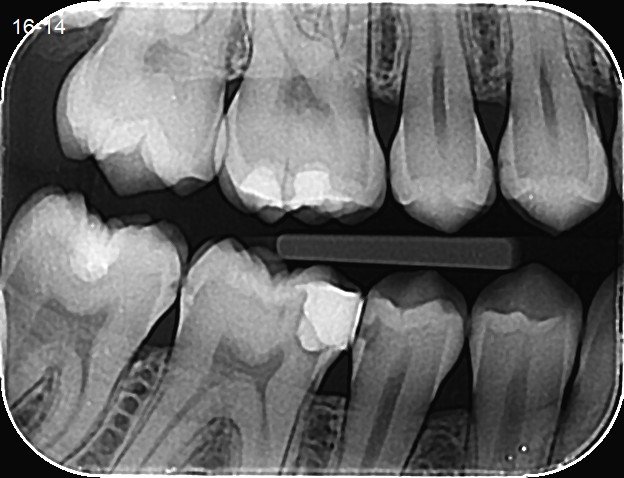

Što su to Bitewing snimke i zašto služe?

Bitewing snimke (ili retroalveolarne snimke) su vrsta dentalnih rendgenskih snimaka koji se koriste u stomatologiji za dijagnostiku problema s zubima i okolnim tkivima. Naziv “bitewing” dolazi od toga što pacijent prilikom snimanja grize mali držač (krilce) koji drži rendgenski film ili senzor na mjestu.

• Dijagnostika karijesa: Bitewing snimke omogućuju otkrivanje karijesa između zuba (interproksimalni karijes) koji se ne vidi golim okom.

• Procjena stanja ispuna: Pomažu u provjeri kvalitete i stanja postojećih ispuna.

• Otkrivanje promjena na kosti: Mogu pokazati gubitak kosti oko zuba, što je često povezano s parodontalnim bolestima.

• Pregled kruna zuba: Prikazuju strukturu zuba iznad linije desni.

• Snimka obuhvaća krune gornjih i donjih zuba jedne strane usta, obično lijeve ili desne.

• Za razliku od panoramskih snimaka (koji prikazuju cijelu čeljust), bitewing snimke fokusiraju se na manji dio usta i pružaju detaljniji prikaz zuba i međuzubnih prostora.

• U usporedbi s periapikalnim snimkama (koje pokazuju cijeli zub, uključujući korijen), bitewing snimke prikazuju samo krune i dio korijena.

Primjer bitewing snimke